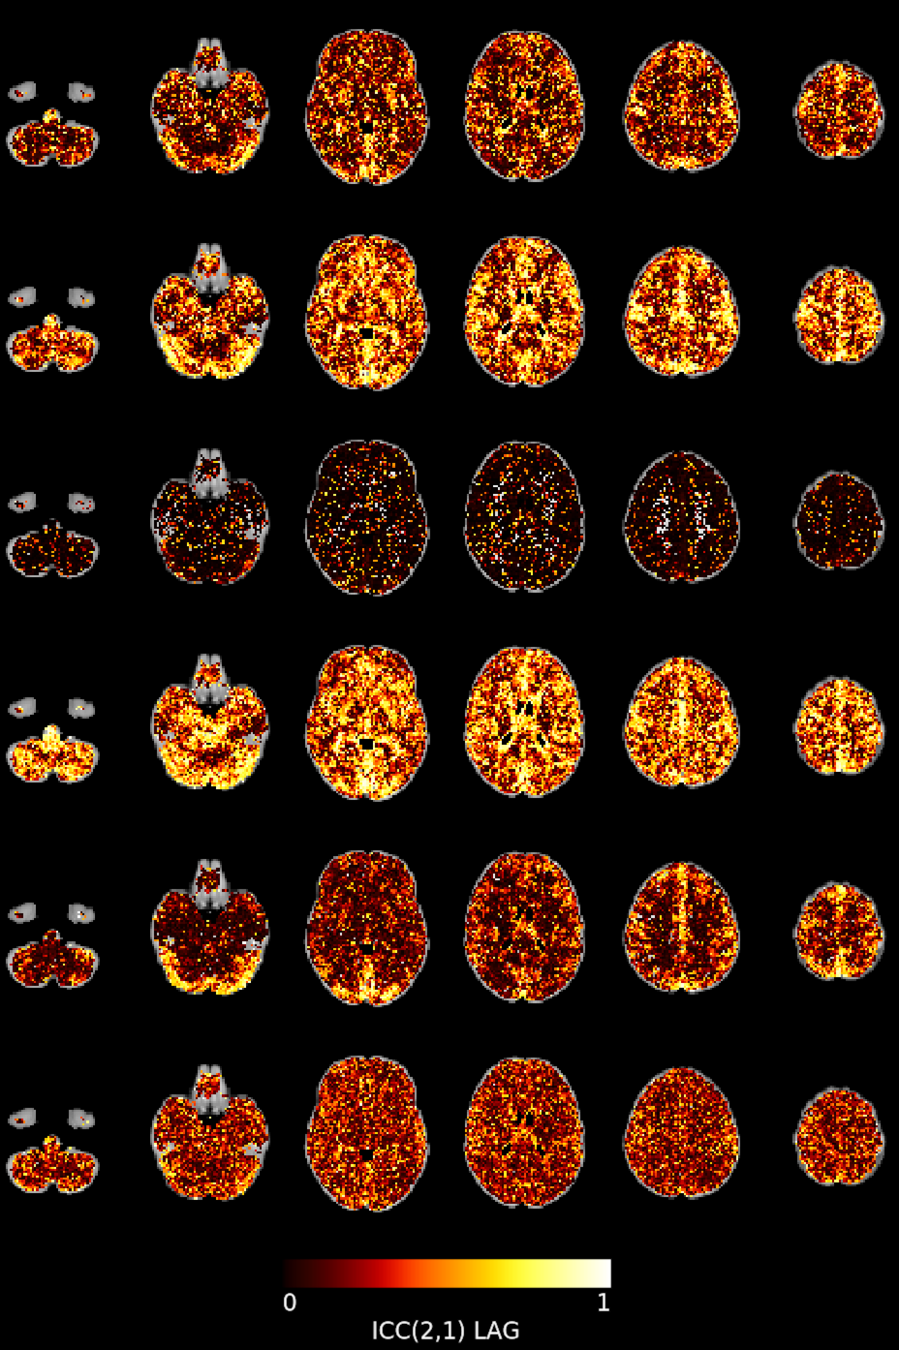

Results: lag maps

Moia et al. 2021 (NeuroImage)

Results: lag maps

Moia et al. 2021 (NeuroImage)

Reliability [ICC (2,1)]

Moia et al. 2021 (NeuroImage)